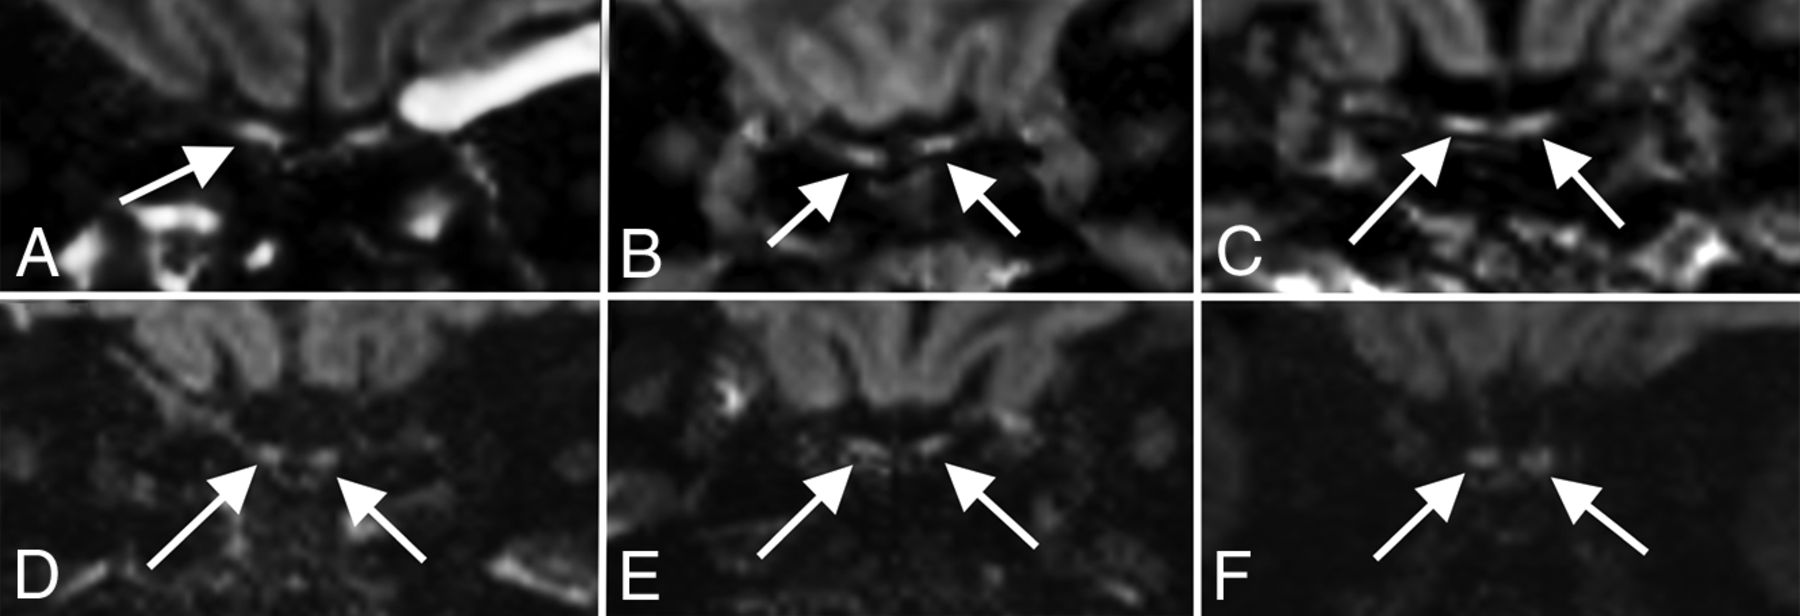

Given the prevalence of anosmia in patients with COVID-19,21⇓-23 our department added thin-section coronal T2 imaging through the olfactory bulbs to brain MRIs for all patients with COVID-19 in whom clinical status allowed the additional scan time. A total of 13 examinations (12 patients; mean age, 58 years; 6 women) included both diagnostic olfactory bulb sequences and high-resolution 3D-T2 FLAIR sequences; these studies were included in a separate systematic review (S.B. Strauss, unpublished data, May 2020). Briefly, no patient demonstrated changes in olfactory bulb volume. However, 4 of 12 patients demonstrated abnormally increased olfactory bulb signal on postcontrast T2 FLAIR, which may reflect intrinsic T2 prolongation or, potentially, contrast enhancement (Fig 5). No abnormalities were identified along the olfactory clefts within this cohort to correlate with findings reported in a prior case report of olfactory cleft obstruction in a patient with COVID-19 with anosmia.15 One of the 4 patients with olfactory bulb signal abnormality had documented anosmia, but for the other 3 patients, there was no clinical documentation addressing either the presence or absence of anosmia.

Olfactory neuritis. Six patients with COVID-19 with coronal T2-FLAIR postcontrast images. A 48-year-old woman (A) demonstrates hyperintense signal in the right (arrow) greater than left olfactory bulbs. A 52-year-old woman (B) and a 62-year-old man (C) demonstrate symmetric hyperintense signal in the olfactory bulbs (arrows). For comparison, 3 different patients (D–F) in our cohort with normal olfactory bulbs (arrows) are included.